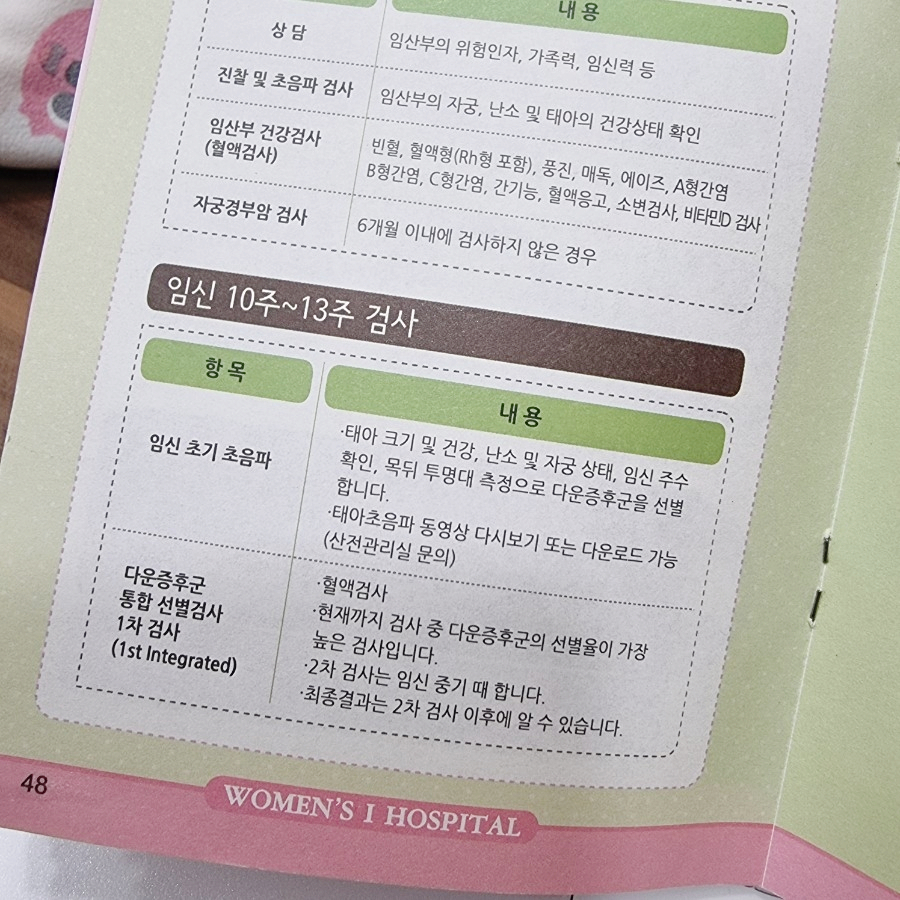

1차 기형아 검사 시기는 통상 임신 10~13주로 이루어지며, Nucchal translucency(NT: 목덜미 투명대) 측정, 통합 분석 검사라고도 합니다.초음파로 태아의 목 둘레 투명대의 두께를 측정하여 염색체 이상으로 인한 기형 여부를 조사하는 것입니다.

통합분석검사 1차 Integrated test(NT, PAPP-A, AFP, HCG, UE3, Inhibin-A) 80~93%의 정확도를 보이며 이를 통해 양수검사, 융모막검사의 필요성을 줄이고 태아 손상을 최소화하였습니다.현재까지 다운증후군 선별률이 가장 높은 검사라고 합니다.

평소에 하고 있던 초음파를 보도록 하는 검사입니다.초음파를 보면서 태아의 크기, 건강, 난소, 자궁 상태, 임신 주수 확인, 목 뒤쪽 투명대 측정으로 다운증후군을 선별합니다.그리고 혈액검사도 함께 실시하여 1차 2차 기형아 검사까지 모두 마친 후에 정확한 결과를 알 수 있습니다.